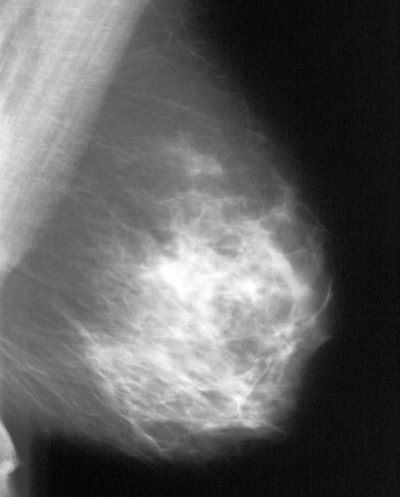

![]() |

| Very dense, glandular pattern seen on mammography in most young women. Breast cancer is extremely hard to find when the breast pattern is this dense, with almost no fatty tissue present. Image courtesy of Dr. Michael Linver. |